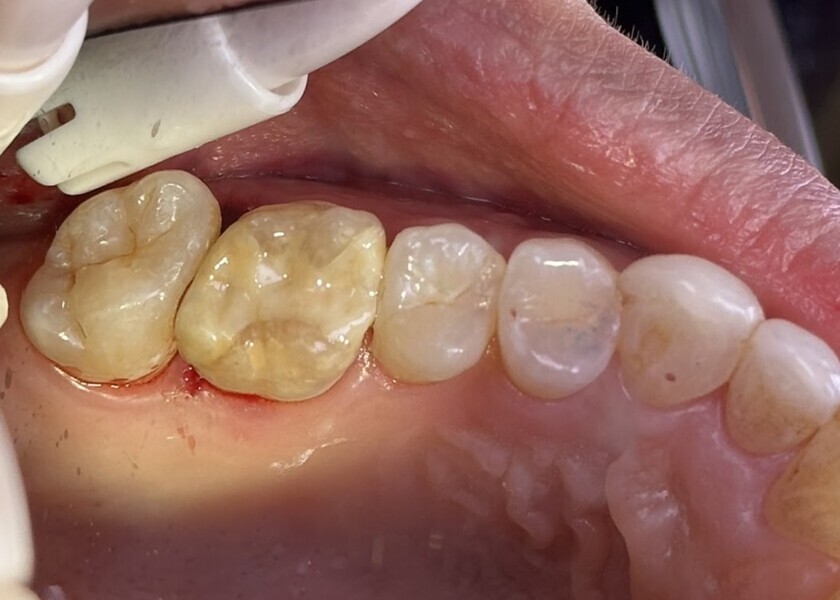

Fig. 3: Pre-op periapical radiograph demonstrating recurrent caries on the distal aspect of the maxillary right first molar.

Fig. 4: Clinical view of the occlusal surface of the maxillary right first molar showing the composite present.

A 46-year-old female patient presented for a recall hygiene appointment, and bitewing radiographs were taken. Proximal caries was noted on the distal aspect of the maxillary right first molar radiographically. A periapical radiograph was taken to further evaluate the tooth, and distal recurrent caries was confirmed (Fig. 3). Clinically, a chipped composite restoration on the tooth with clinical signs of composite wear on the mesial–occlusal and occlusal–palatal aspects was noted, as was distal secondary caries (Fig. 4). Removal of the failing composite and of the recurrent caries and replacement with a 3D-printed ceramic resin inlay in one appointment was recommended. The patient accepted treatment, and time in the schedule allowed treatment to be done that day.